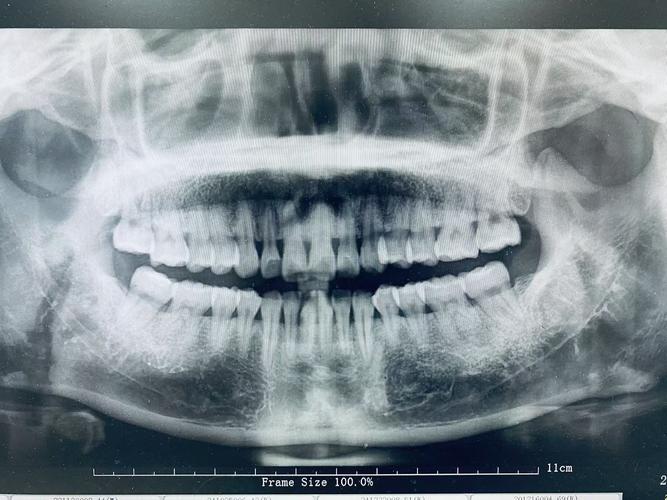

| 全景片(曲面断层片) | 观察全口牙齿排列、牙根形态、牙槽骨高度、第三磨牙位置、颌骨病变及发育情况 | 优点:辐射低(约0.007mSv)、费用低、可显示全口牙列;缺点:二维重叠、细微结构模糊 | 常规正畸初筛,了解牙齿数目、萌出顺序、牙根有无吸收、牙槽骨整体状况 |

| CBCT(锥形束CT) | 三维重建颌骨、牙齿、神经血管位置,清晰显示埋伏牙方向、牙根与骨皮质关系、上颌窦及下颌管位置 | 优点:三维立体、分辨率高、可任意角度旋转;缺点:辐射高于全景片(约0.1-0.3mSv)、费用高 | 复杂病例(如埋伏牙牵引、正颌手术术前评估、骨量不足需植骨者、颞下颌关节紊乱检查) |

正畸医生需结合全景片、头颅侧位片、CBCT等多源影像,结合临床检查(模型、口内照、面部分析)进行综合解读,对于“牙列拥挤”患者,全景片需观察牙根有无弯曲、吸收,牙槽骨高度是否支持牙齿移动;头颅侧位片需分析拥挤是否由颌骨发育不足(如上颌骨狭窄)导致,以决定是否需要扩弓或拔牙矫治,CBCT则可明确牙槽骨厚度,判断隐形矫治附件粘贴的可行性,或正颌手术中骨块移动的安全范围。

A:全景片虽能显示全口牙列,但属于二维重叠影像,对埋伏牙、牙根与骨皮质关系、颌骨内重要解剖结构(如下牙管、上颌窦底)的显示存在局限,CBCT可三维重建颌骨和牙齿,清晰呈现埋伏牙的位置、方向及与邻牙的关系,帮助医生设计精准的牵引方案;对于正颌手术患者,CBCT能模拟骨块移动路径,避免损伤神经血管;对牙根吸收、骨皮质穿孔等细微病变的检出率也显著高于全景片,复杂病例需通过CBCT获取更全面的信息,确保治疗安全与效果。